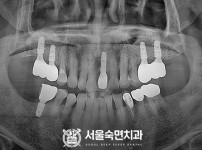

임플란트-전후사진3